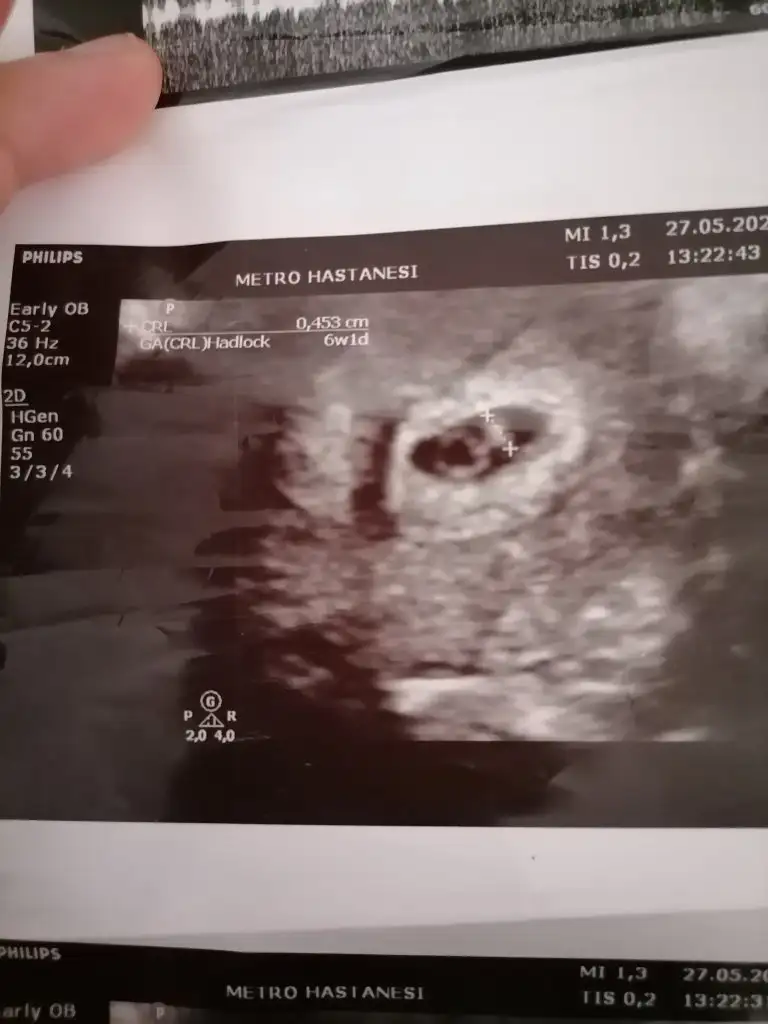

benimkini de görmediniz sanırım.6+2 karından ultrasonmerhaba.bi tahminde benim için bulunabilirmisiniz acaba :)

bu olur mu?6+2 karındanfotoğrafı yakınlaştırmadan çekip atabilir misiniz

paşa gibibu olur mu?6+2 karından